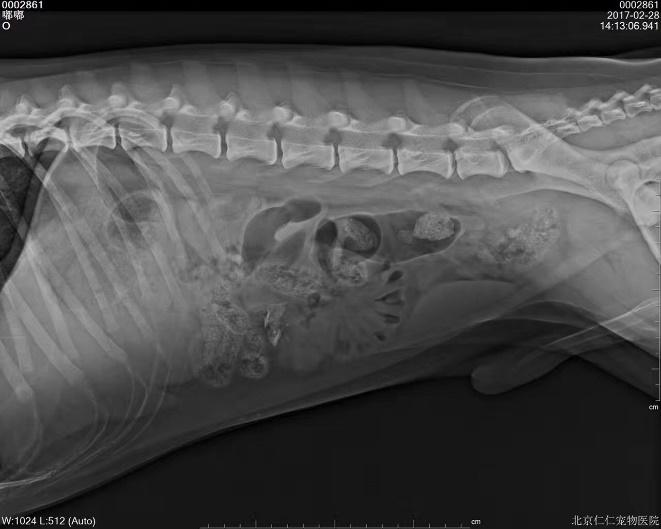

b. X射线检查:对于阻线性较强的物质(如金属、骨头)较容易辨别,对于阻线性与组织密度相似的物体较难确定,但是可以通过消化道灌服造影剂判断是否有阻塞或可包裹物体。

胃的正常大小:胃位于前腹部,隔和胆脏之后。胃排空时位于肋弓以内;从腹底算起,胃的腹侧缘大约在腹腔深度的1/3处。胃充盈时,胃向后向下延伸,与横结肠和腹底部相接。

摆位对

钡餐4小时后胃内未排空(家猫,线性异物)